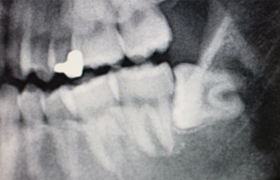

親知らず

親知らずとは前から数えて8番目の歯で正式には第3大臼歯、または智歯といわれます。

この親知らずが横向きに生えてきたりすると周りの歯肉が炎症を起こします。これを智歯周囲炎といいます。

痛くなったり腫れてきたり、さらに症状が強くなると口が開きにくくなることもあります。また親知らず自体が虫歯になったり隣接する第2大臼歯を虫歯にしたり、様々なトラブルを起こす場合が多い歯です。

症状と親知らずの状態から保存した方が良いか、抜歯した方が良いかよく診断し処置いたします。